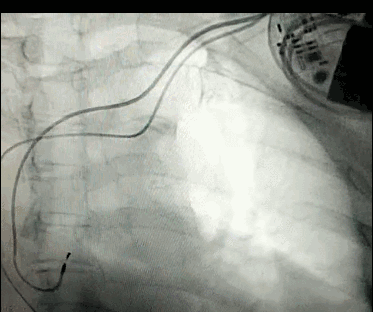

腦血管成像的“金標準”!——DSA三部曲之技術篇

DSA是將造影劑注入需要檢查的血管中,使血管顯露原形,然后通過系統(tǒng)處理,使血管顯示更加清晰,便于醫(yī)生診斷或進行手術。